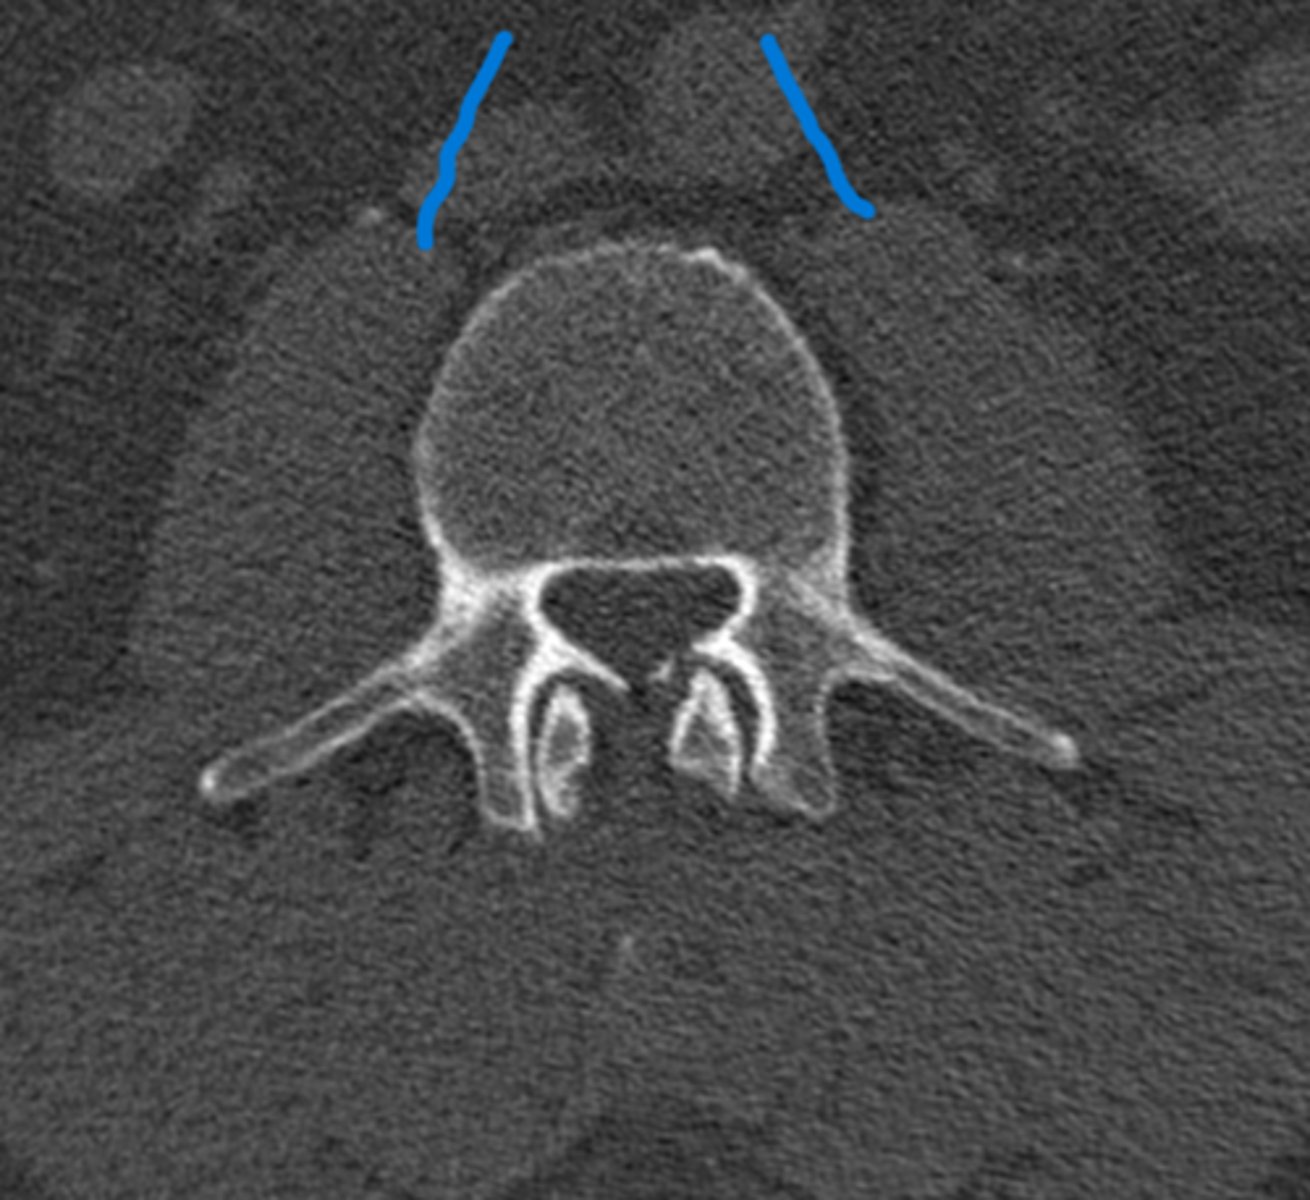

1) Body

2) Vertebral foramen

3) Lamina

4) Pedicle

5) Transverse process

6) Superior articular process

7) Spinous process

Name all numbered structures

1) Body

2) Pedicle

3) Spinous process

4) Lamina

5) Transverse process

Name all numbered structures

Spinous processes

What structures are these lines pointing to

Blue line- vertebral bodies

Red line- spinal canal

What is the blue line pointing to and what is the red line pointing to